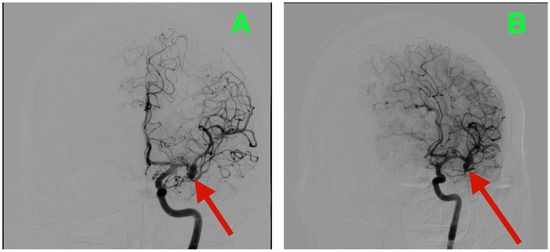

Immediate postoperative neuroimaging was not obtained, consistent with the institutional protocol in neurologically stable patients after uncomplicated microsurgical aneurysm clipping. Predefined triggers for urgent imaging—any new focal deficit, sustained escalation of headache, decline in level of consciousness, or refractory hypertension—did not occur during inpatient monitoring. The patient was discharged on postoperative day three with instructions regarding blood pressure control, wound care, graded activity progression, and scheduled outpatient visits at two weeks, six weeks, and three months. At interval clinic assessments, he reported complete resolution of the preoperative vascular-pattern headaches, absence of exertional provocation, and restored confidence in balance and sustained fine-motor endurance during overhead tasks. The neurological examination remained normal and unchanged from the inpatient baseline. At three months, non-contrast cranial CT (Figure 3) demonstrated the expected clip artifacts at the MCA bifurcation and proximal M1 with preserved parenchymal attenuation throughout the superior division territory and within the internal capsule and dorsal basal ganglia, without encephalomalacia, hydrocephalus, or extra-axial collection, radiologically corroborating durable exclusion of both aneurysms with intact branch and perforator perfusion. Functional outcomes were congruent with the radiology and clinical course: the patient met criteria for complete independence with a modified Rankin Scale score of 0 and National Institutes of Health Stroke Scale (NIHSS) of 0 at discharge and again at the three-month follow-up.

Figure 3.

Three-month postoperative non-contrast cranial CT. (A) Axial non-contrast CT at the level of the left MCA bifurcation/insular apex, showing the expected clip artifact centered on the bifurcation–proximal M1 complex, with preserved cortical ribbon along the opercular–insular corridor, normal attenuation of the internal capsule and dorsal basal ganglia, and no peri-clip hypodensity, hemorrhage, or mass effect. (B) Axial non-contrast CT at a slightly higher level through the superior division territory, demonstrating intact suprasylvian cortex and corona radiata without encephalomalacia or gliotic change. Ventricles and basal cisterns are normal in size and configuration, midline is preserved, and there is no extra-axial collection.

The durable resolution of preoperative micro-asymmetries, together with structurally preserved dominant-hemisphere parenchyma on the three-month CT, supports effective clip reconstruction with maintained superior-division branch flow and uncompromised lenticulostriate perfusion.